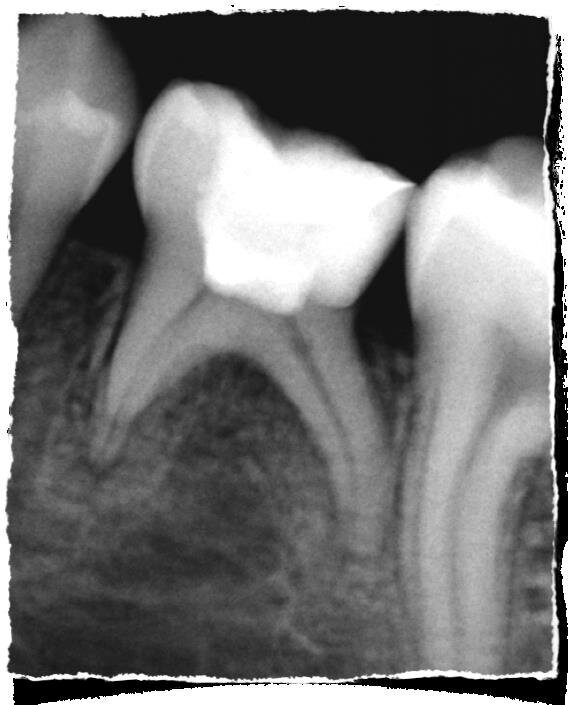

Il trattamento endodontico del dente deciduo comporta principalmente due procedure: la pulpotomia e la pulpectomia. Non è consigliabile eseguire degli incappucciamenti della polpa poiché dalla letteratura si evince che la percentuale di successo a lungo termine è minore rispetto a quelle che si ottengono nei trattamenti di pulpotomia. La pulpotomia è il trattamento endodontico più utilizzato negli elementi decidui che mostrano l’interessamento della sola polpa camerale in seguito all’esposizione accidentale di una porzione di essa dovuta a un processo carioso o a un trauma, purché il dente risulti asintomatico per i segni clinici di sofferenza pulpare e non presenti segni radiografici di lesioni periapicali.

Un sanguinamento profuso dopo 3 minuti da una indicazione di iperemia pulpare ed è consigliabile procedere ad un trattamento di pulpectomia. Ottenuta una adeguata emostasi, senza sostanze promuoventi, si procede al posizionamento in camera pulpare del materiale scelto. Nel tempo sono stati utilizzati svariati materiali, come il formocreosolo e la glutaraldeide, che però non vengono più utilizzati per la loro cancerogenicità. Attualmente i migliori in commercio per un trattamento di pulpotomia sono i cementi Portland, gli MTA ed i materiali bioceramici.

Dalla letteratura si evince come questi materiali diano una buona risposta tissutale con delle percentuali di successo, a medio e lungo termine, di circa il 90-98%. In base al tipo utilizzato si potrà procedere, nella stessa seduta o nella successiva, alla ricostruzione definitiva, utilizzando i sistemi adesivi presenti in commercio e materiale composito.

La pulpectomia è un trattamento che prevede la rimozione dell’intero organo pulpare, sia coronale che radicolare. È indicata nei casi in cui la polpa è vitale ma irreversibilmente infiammata o non vitale a causa di lesioni cariose avanzate o di traumi. Il fine del trattamento endodontico è quello di controllare l’infezione e quindi eliminare i batteri patogeni del sistema canalare.

La metodica prevede il trattamento del sistema canalare finalizzato a promuovere una buona penetrazione degli irriganti mediante una alesatura con strumenti a bassa conicità al fine di non creare un eccesivo indebolimento delle già sottili pareti radicolari, dovuto al processo di rizalisi in atto. I materiali utilizzati per la chiusura devono essere esclusivamente riassorbibili ma in grado di garantire un adeguato sigillo del terzo medio-coronale del canale radicolare onde evitare possibili contaminazioni batteriche del sistema endodontico.